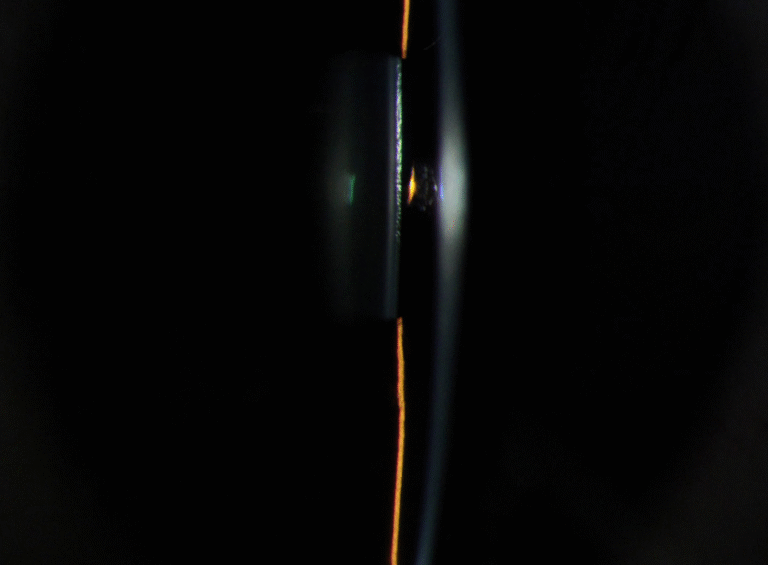

Integrated Filters

Built-in Yellow Filter

The PSL-9000 features a built-in yellow barrier filter that works in combination with cobalt blue illumination to reveal sodium fluorescein staining patterns on the cornea and ocular surface with exceptional clarity.

Precision Optics

Premium Optical System

High-resolution visualization across a wide range of magnifications. Multi-coated optics deliver distortion-free anterior segment imaging for confident clinical assessment.

- 5 Step Magnification: 6×, 10×, 16×, 25×, 40×

- 24 Megapixel SLR Camera

- Automatic Digital Optimization

- Automatic Eye Position Recognition for Digital Acquisition